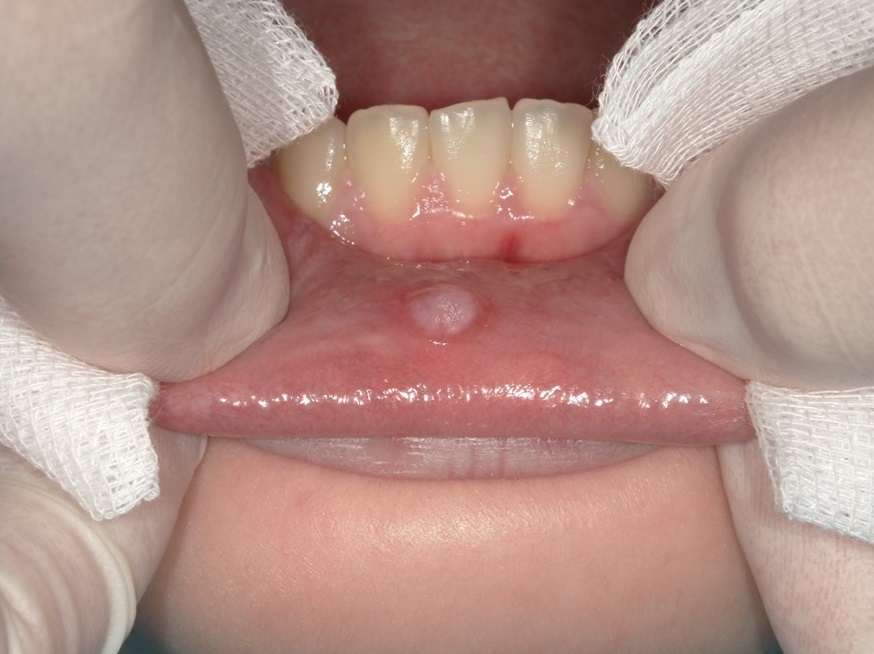

②粘液嚢胞は唇やほっぺの内側にできる半透明の膨らみが特徴です。膨らんではつぶれてを繰り返したり、数週間消えないはような膨らみは粘液嚢胞が疑えます。積極的に受診して精査しましょう。これも見た目が重要で、これらは大概、受診された際に臨床診断できます。当院ではこの症例が中でも一番多い印象があります。

処置としては局所麻酔下に摘出を行います。摘出したものは病理検査に出して確定診断を行います。